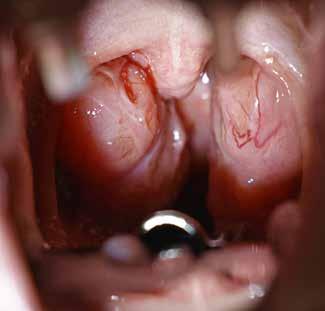

Normotrofe tonsiller

Fig. 2. Eksempel på egale, normotrofe tonsiller (T) beliggende mellem forreste ganebue (FG) og bagerste ganebue (BG). Uvula (U) midstillet og oropharynx bagvæg (O) ses.

Fig. 2. Example of normotrophic tonsils (T) between anterior (FG) and posterior (BG) tonsillar pillar. Uvula (U) is centered and the posterior oropharyngeal wall (O) is visualized.

tonsilhypertrofi hos en 3-årige pige. Tonsillerne (T) ses prominerende medialt for forreste ganebue (FG) mod uvula (U). Oropharynx bagvæg (O) ses i baggrunden. B. Svær tonsilhypertrofi hos en 3-årige pige. Tonsillerne (T) er udtalt hypertrofe og strækkende sig medialt mod uvula (U) og minimalt dækket af forreste ganebue (FG). Oropharynx bagvæg (O) ses i baggrunden.

Fig. 1 A. Mild tonsillar hypertrophy in a 3-year-old. The tonsils (T) extend towards the uvula (U) and are partially covered by the tonsillar pillar (FG). The posterior oropharyngeal wall (O) is visualized. B. Severe tonsillar hypertrophy in a 3-year-old. The tonsils (T) extend towards uvula (U) and only a small portion is covered by the tonsillar pillar (FG). The posterior oropharyngeal wall (O) is visualized.

Fig. 1. A. Let